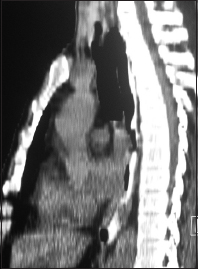

| Figure 2 Computed tomography of thorax coronal view showing large subcarinal node